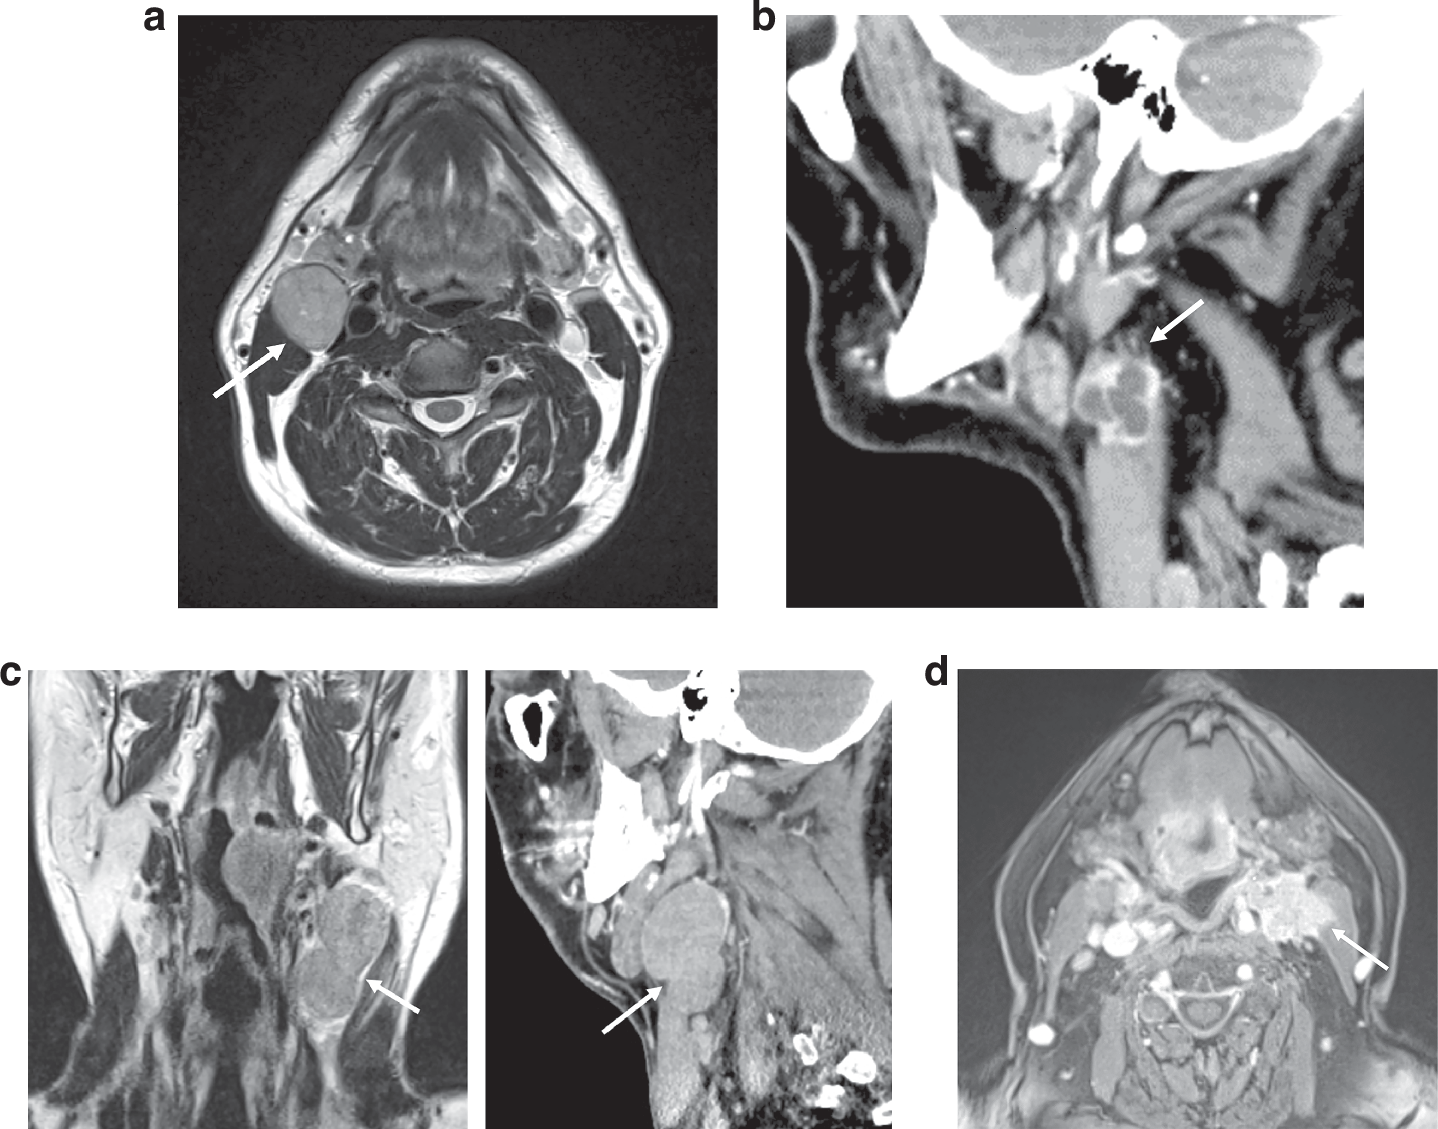

Fig. 1: 4-point scale used to grade iENE.

a Grade 0 iENE: Axial T2 MRI. Well-defined metastatic Level II node, clear perinodal fat (arrow). b Grade 1 iENE: Sagittal CECT. Metastatic Level II node with an irregular nodal margin + perinodal fat stranding (arrow). c Grade 2 iENE: Coronal T2 MRI + sagittal CECT demonstrating coalescence of metastatic Level II + III nodes (arrow). d Grade 3 iENE: Axial T1FS+c MRI demonstrating definite invasion of a metastatic Level II node into adjacent structures. Note the direct infiltration of sternocleidomastoid muscle (arrow)